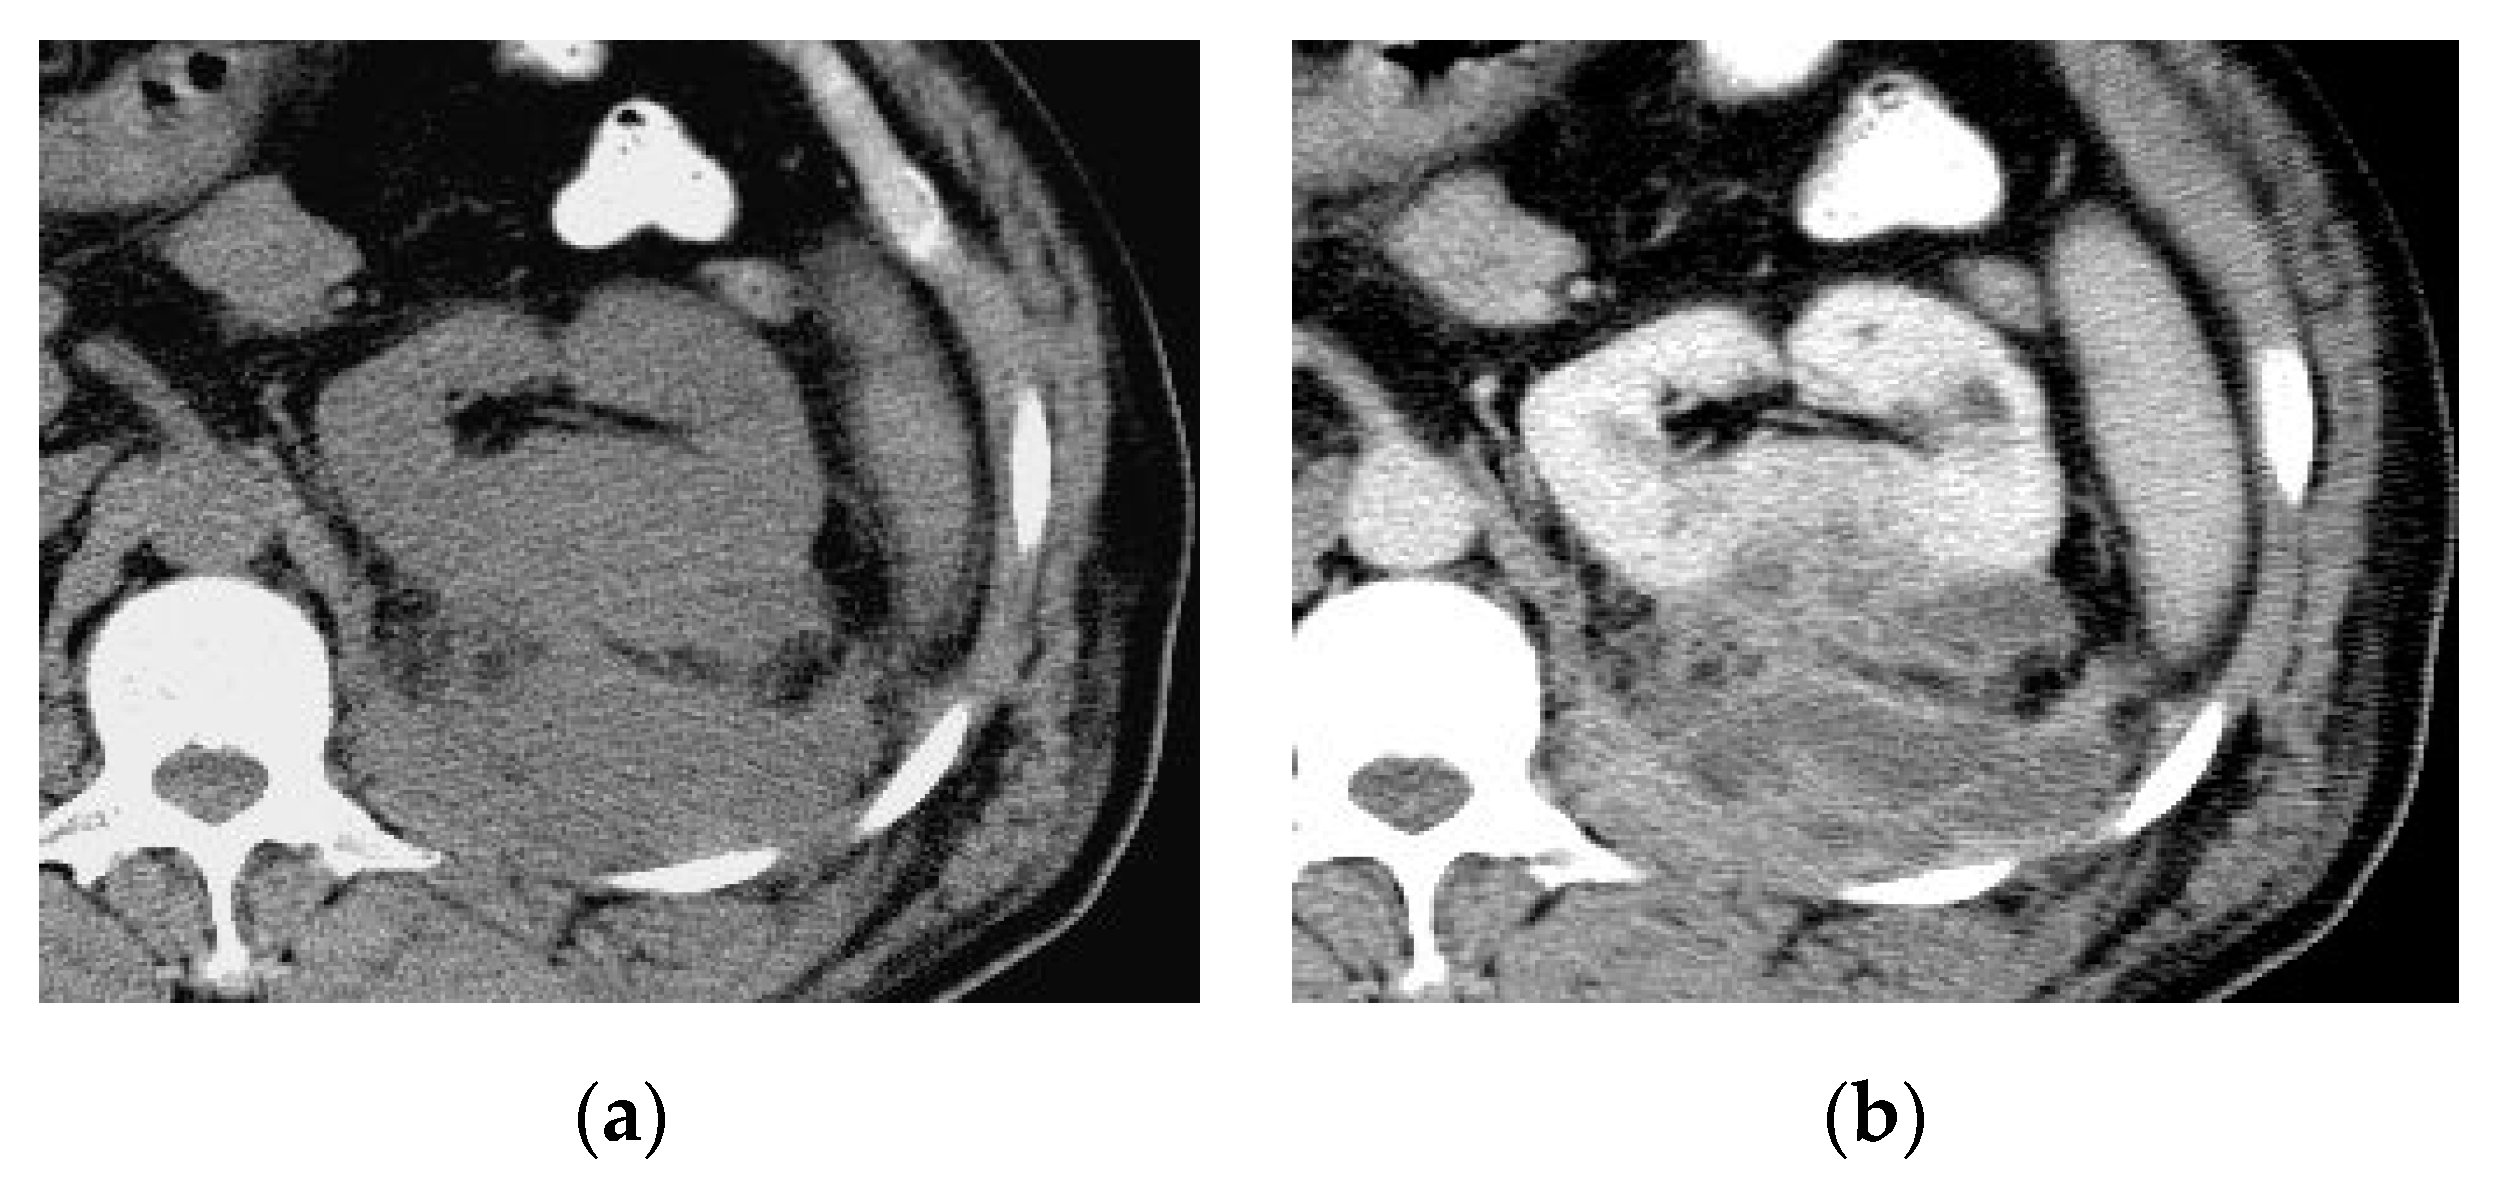

2.1. Acute Pyelonephritis

| Acute pyelonephritis | Wedge shaped hypo-enhancing areas or striated nephrogram pattern. Perinephric fat stranding and thickening of Gerota’s fascia. |